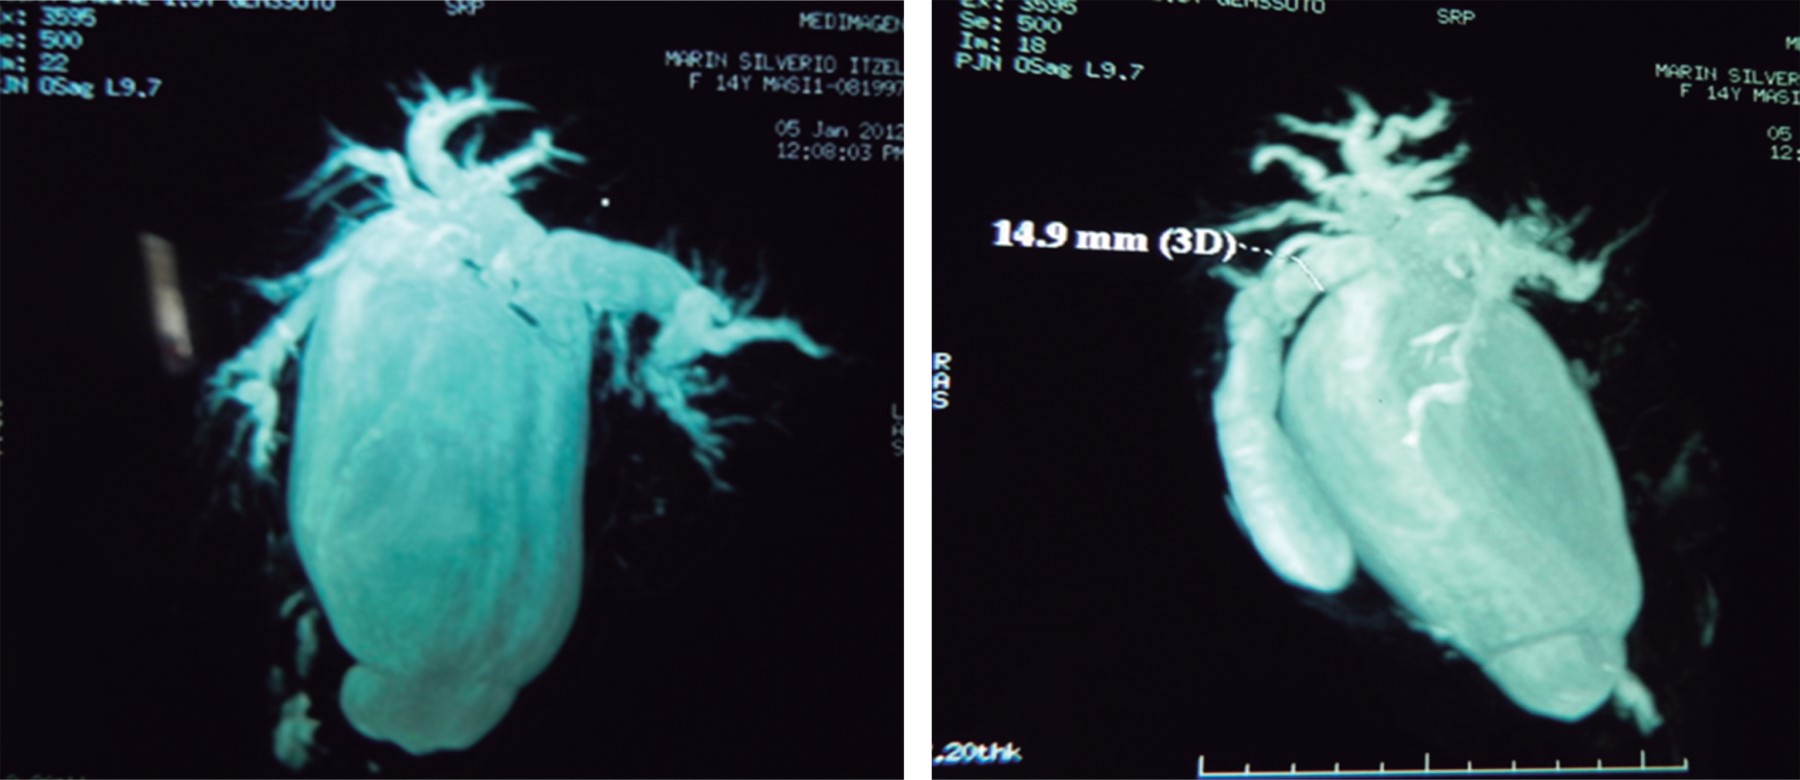

Caso clínico 1: femenino de 14 años, cuatro años de evolución con dolor tipo cólico en hipocondrio derecho. Cuatro meses previos a su ingreso presentó episodios más frecuentes, agregándose ictericia, coluria, acolia, náuseas y vómito. Ingresó con ictericia, dolor a la palpación en hipocondrio derecho y epigastrio, y una tumoración de aproximadamente 15 × 15 cm. Las pruebas de función hepática mostraron hiperbilirrubinemia mixta (bilirrubina total: 7.1 mg/dl, bilirrubina directa: 3.7 mg/dl, aumento de la fosfatasa alcalina: 651 U/l). El ultrasonido reveló colecistitis litiásica, coledocolitiasis versus quiste de colédoco; la tomografía axial computarizada: colecistitis litiásica y dilatación quística de la vía biliar (Figura 1). La colangiorresonancia mostró un quiste de colédoco de 72 mm con dilatación de la vía biliar intrahepática (Figura 2). Se realizó cirugía electiva, se encontró vesícula biliar con litos y un quiste de colédoco tipo I de la clasificación de Todani adherido a duodeno de 17 × 10 × 10 cm (Figura 3).

Figura 1

Figura 2